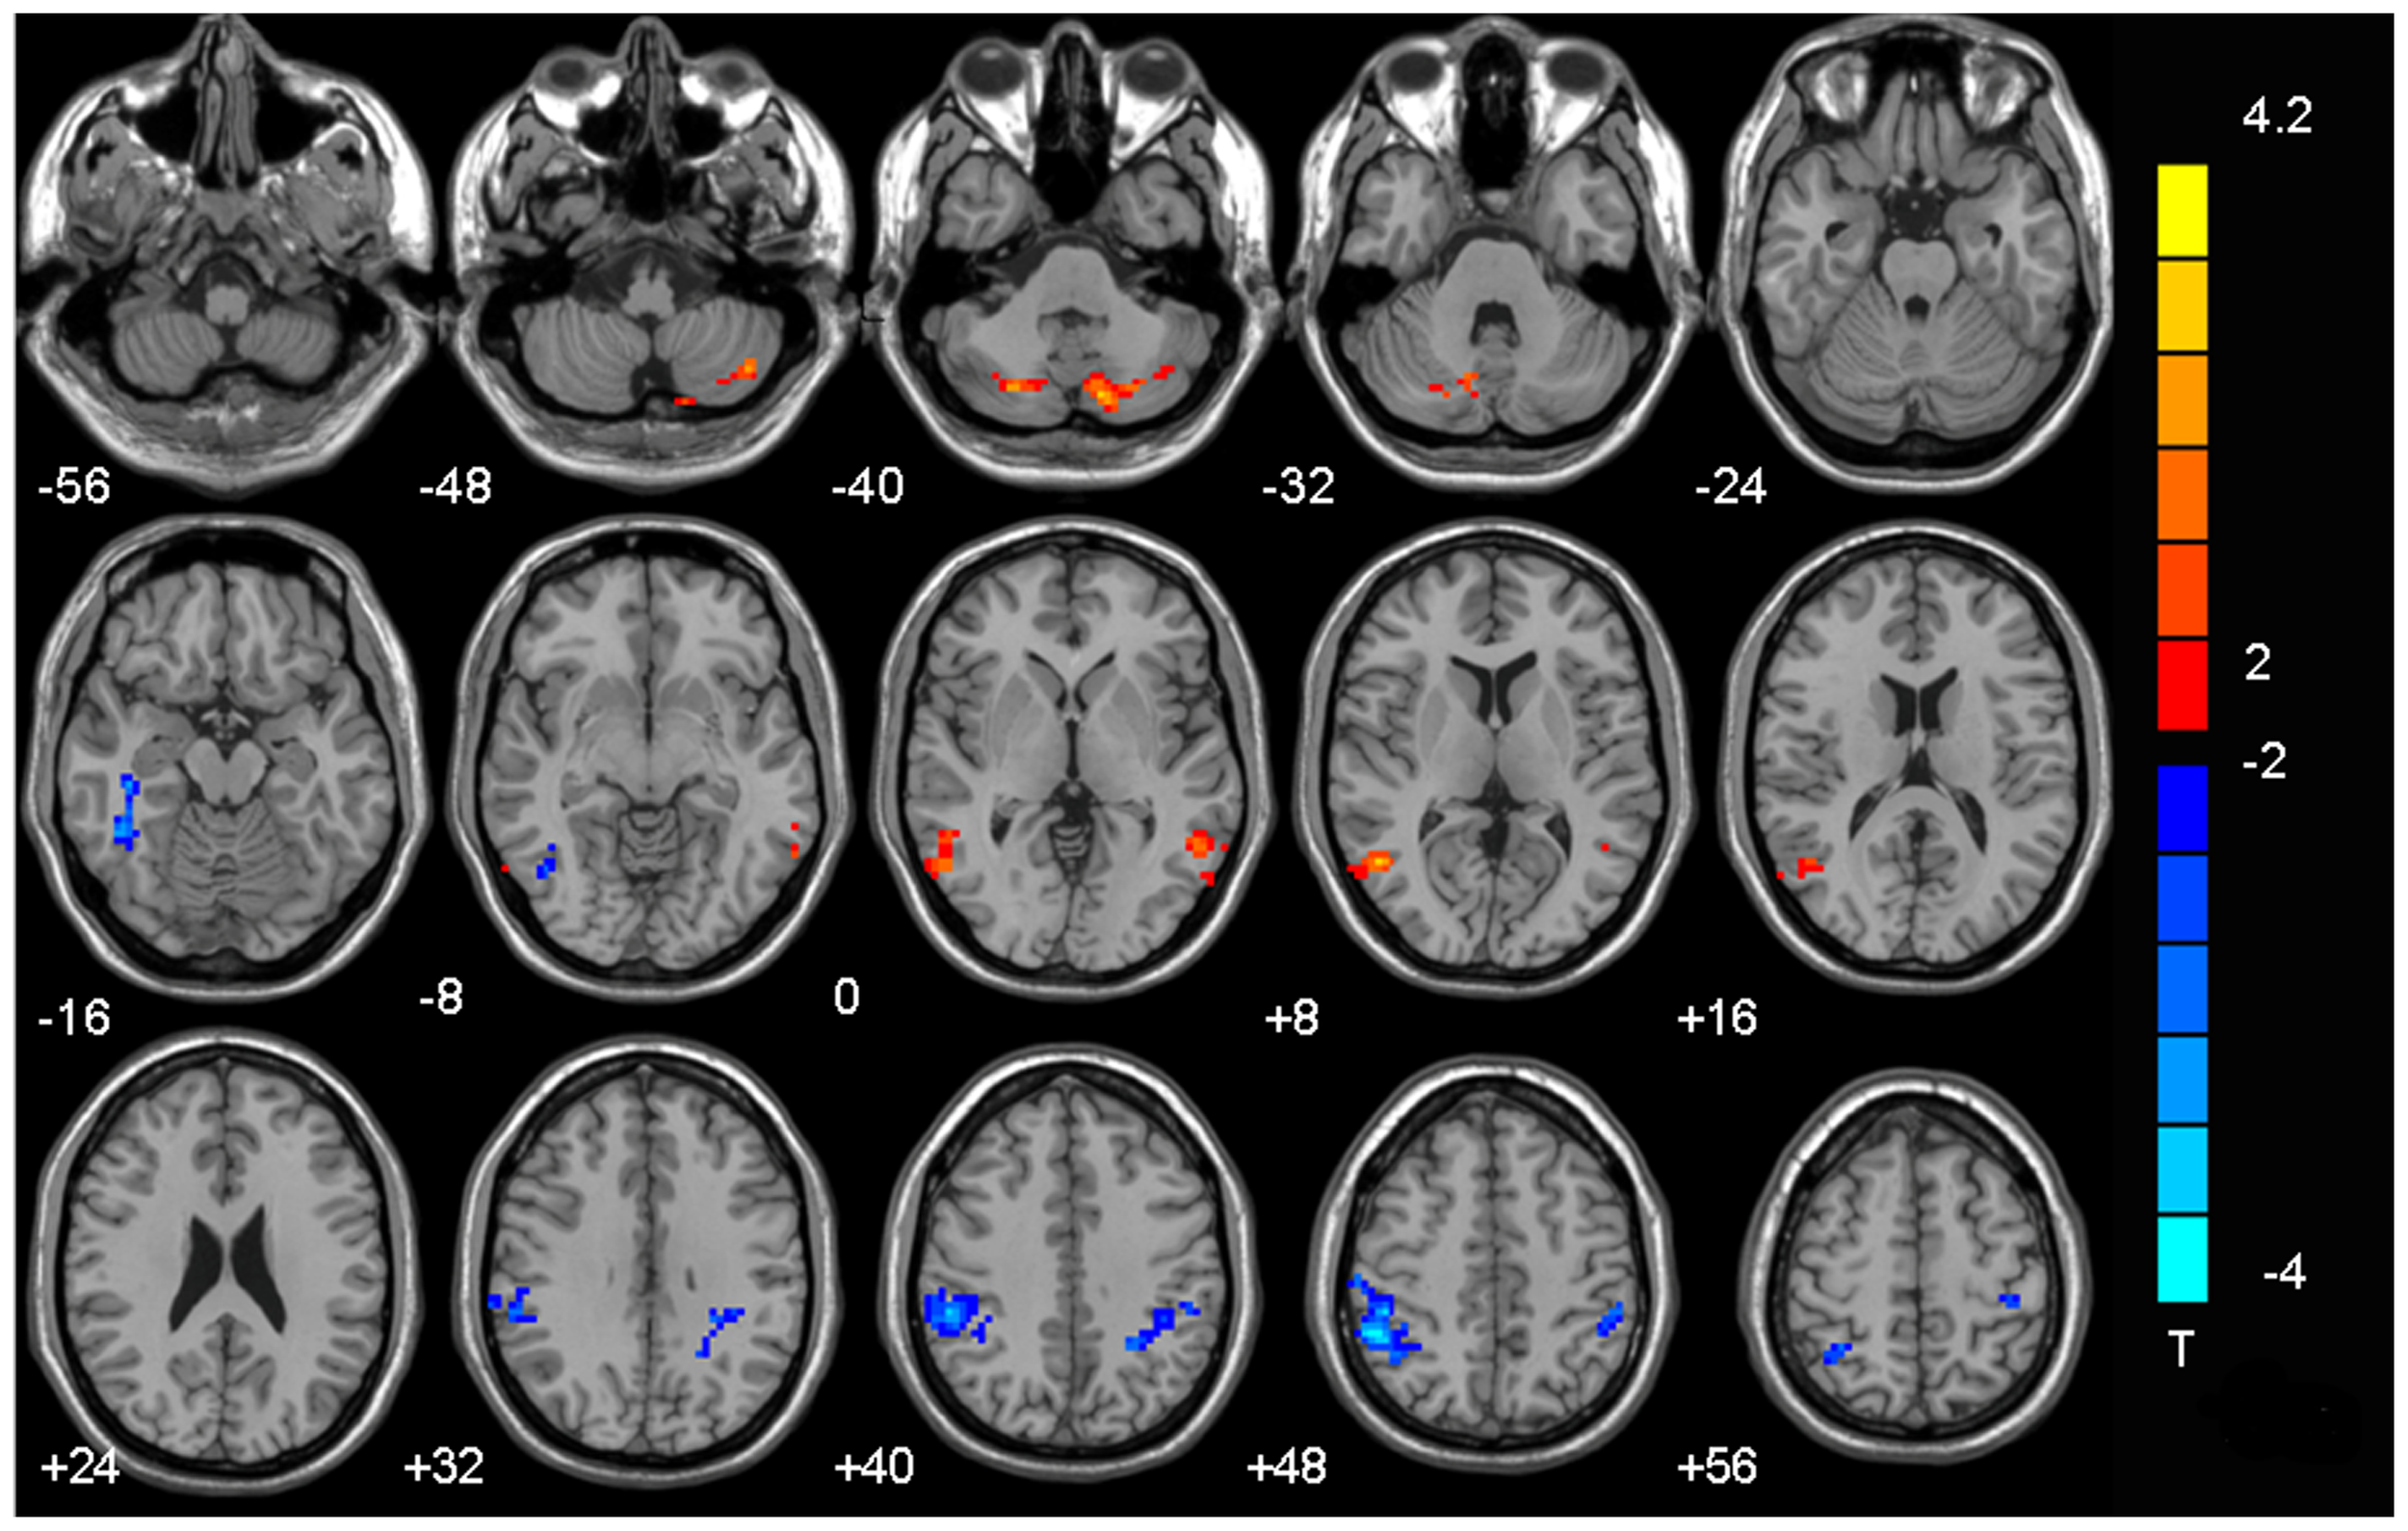

Figure 2.0

This brain image shows areas where connectivity significantly relates to the severity of Internet Gaming Addiction in adolescents. Red regions indicate increased connectivity, meaning these parts of the brain become hyper-responsive, reinforcing impulsive reward-seeking behaviour. Blue regions show decreased connectivity, suggesting weaker brain signals in areas responsible for emotional control and decision-making. In plain English, red dots mean the brain is overly driven to seek immediate digital rewards (likes, games, notifications), while blue dots mean it's less capable of effectively regulating emotions and making good decisions under stress or distraction (Hong et al., 2013).